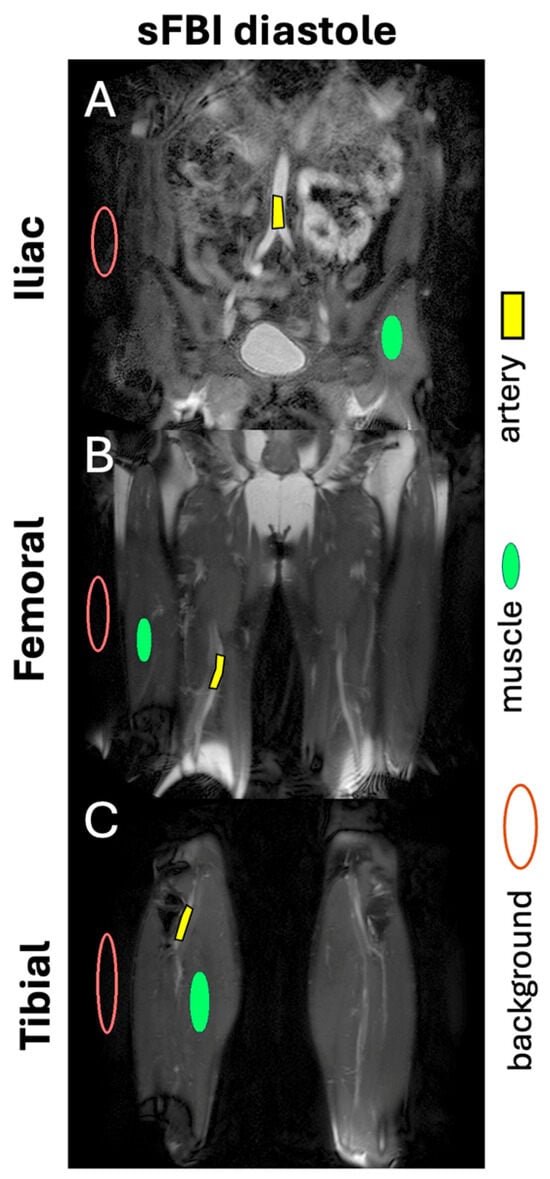

2. Materials and Methods

3. Results